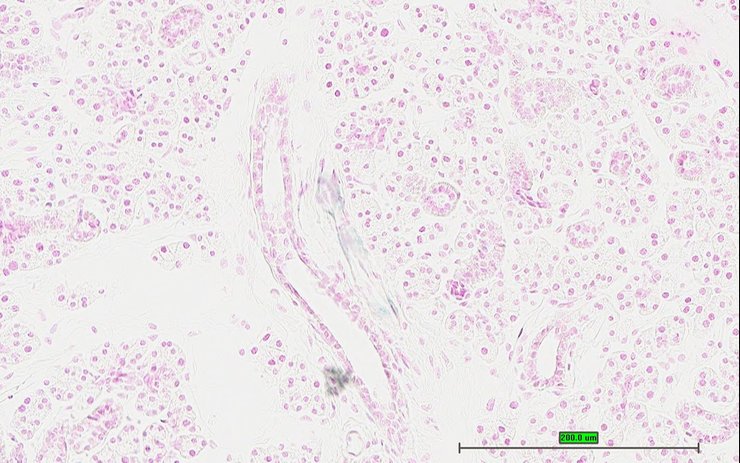

TS28: testis Present UC Davis_1883728

Specimen UC Davis_1883729: postnatal adult; Dmp1tm1.1(KOMP)Vlcg/Dmp1+ (more )